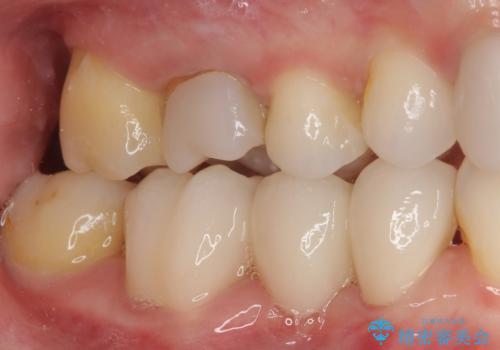

- 上下前歯のデコボコと奥歯の欠損を気にして来院された患者様です。

右下の欠損分は奥歯が倒れ込んでスペースがなくなっていたため、矯正治療により本来の位置に歯を移動させ、オールセラミックブリッジによる欠損補綴治療を行うこととしました。

全顎的にセラミッククラウンが多く装着されているため、インビザラインによる矯正治療を行うこととしました。

右下は移動量が多いため、十分な移動が達成されない場合はワイヤー装置を使用する予定としておりましたが、しっかりとマウスピースを装着してくださったため、前歯とともに十分に歯を動かすことができました。